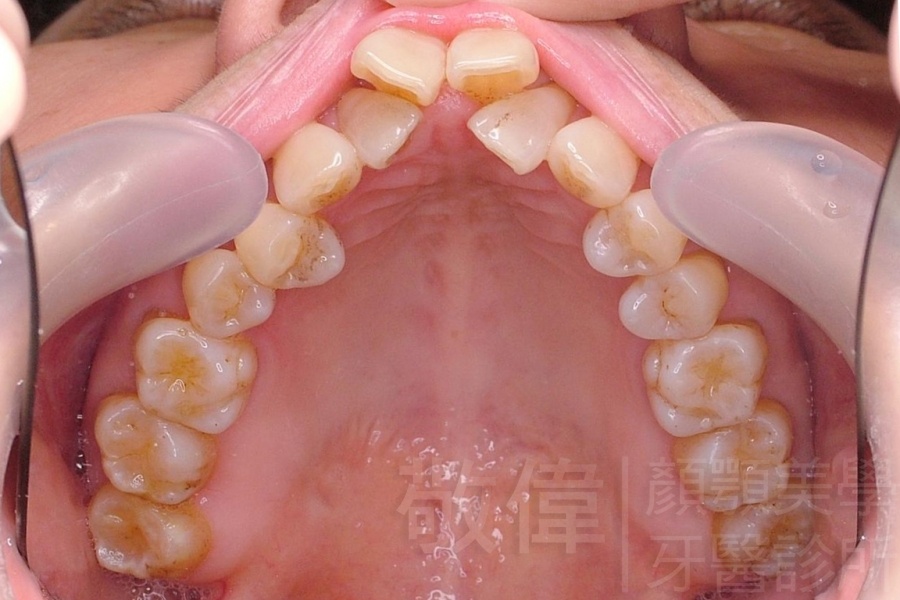

齒顏矯正/上顎暴牙且牙齒極度混亂

矯正前-右   矯正前-正   矯正前-左

矯正前-上   矯正前-下

<個案說明>

上顎暴牙且牙齒極度混亂,經由矯正之後,臉型大幅度改善,牙齒的排列更加的整齊健康。相較於之前眼神充滿精神,自信心展現無遺。